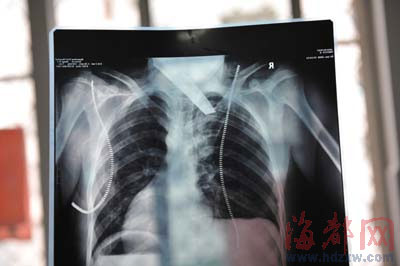

前晚,在第一醫(yī)院急救室,經(jīng)過4個(gè)多小時(shí)的搶救,醫(yī)生將匕首從小勇身上取出,發(fā)現(xiàn)這把匕首的刀尖扎斷了1厘米。由于小勇肺部被刺中,昨天上午,醫(yī)生再次進(jìn)行了3個(gè)多小時(shí)的手術(shù),切除了受傷的部分肺,直到下午,小勇才挺過來!巴α艘灰,現(xiàn)在總算醒了過來!睏钆恳灰箾]睡,守在手術(shù)室外7個(gè)多小時(shí),生怕兒子再醒不過來。不過,由于傷勢(shì)嚴(yán)重,小勇目前戴著氧氣呼吸,仍未脫險(xiǎn)。